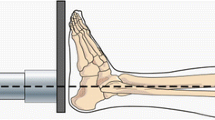

The foot/ankle complex is frequently injured in many types of debilitating events, such as car crashes. Numerical models used to assess injury risk are typically minimally validated and do not account for ankle posture variations that frequently occur during these events. The purpose of this study was to evaluate a finite element model of the foot and ankle accounting for these positional changes. A model was constructed from computed tomography scans of a male cadaveric lower leg and was evaluated by comparing simulated bone positions and strain responses to experimental results at five postures in which fractures are commonly reported. The bone positions showed agreement typically within 6° or less in all anatomical directions, and strain matching was consistent with the range of errors observed in similar studies (typically within 50% of the average strains). Fracture thresholds and locations in each posture were also estimated to be similar to those reported in the literature (ranging from 6.3 kN in the neutral posture to 3.9 kN in combined eversion and external rotation). The least vulnerable posture was neutral, and all other postures had lower fracture thresholds, indicating that examination of the fracture threshold of the lower limb in the neutral posture alone may be an underestimation. This work presents an important step forward in the modeling of lower limb injury risk in altered ankle postures. Potential clinical applications of the model include the development of postural guidelines to minimize injury, as well as the evaluation of new protective systems.

Smolen, C., Quenneville, C.E. A Finite Element Model of the Foot/Ankle to Evaluate Injury Risk in Various Postures. Ann Biomed Eng 45, 1993–2008 (2017). https://doi.org/10.1007/s10439-017-1844-2